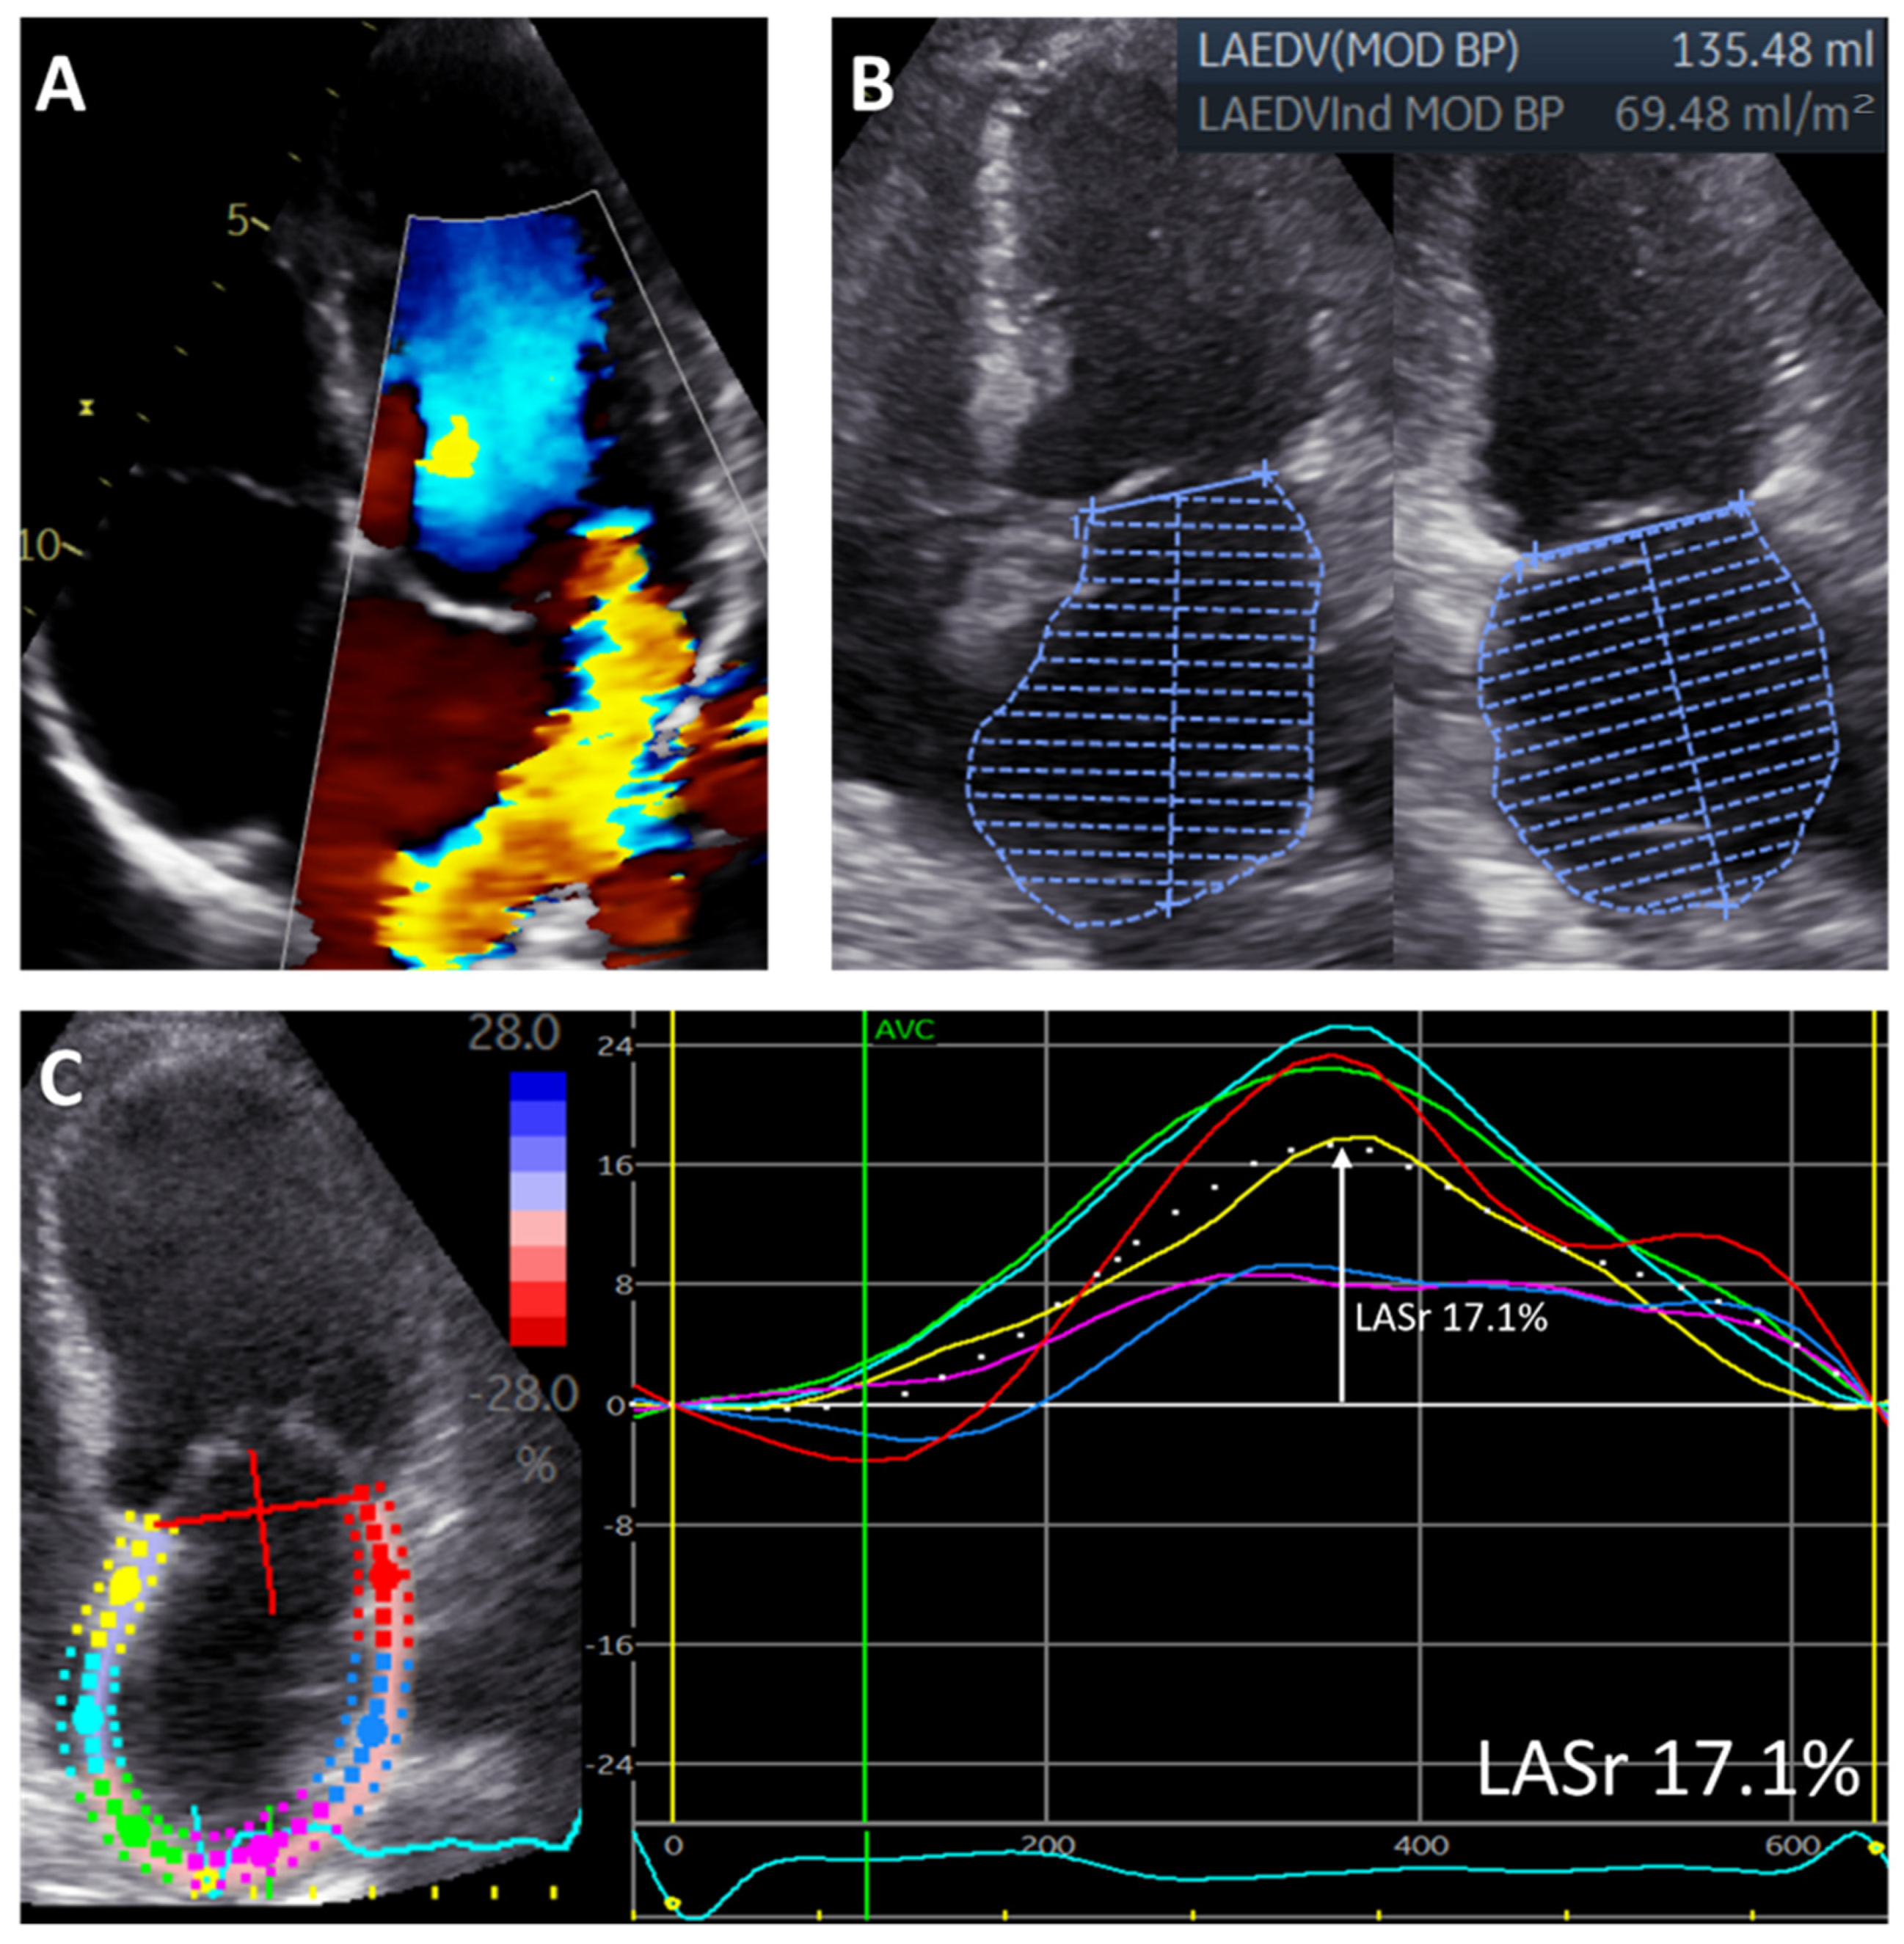

For the assessment of LA function, LA speckle-tracking strain was measured from the apical 4-chamber view with the onset of the QRS complex as the zero-reference point, according to current guidelines [19]. A region of interest was manually drawn along the LA endocardial border when LA was to its minimum volume after atrial contraction, excluding the pulmonary vein ostia and LA appendage. Automatic tracking of the LA wall by the software was visually verified and corrected by adjusting the region of interest or the width of the contour, ensuring appropriate capture of LA motion. LA reservoir strain (LASr) was then measured directly from the resulting LA strain versus time curve (Figure 1). To accurately assess the change in LA function over time, LASr was also adjusted for LAVi, since LA size changed significantly after MV surgery.

Figure 1.

Measurements of left atrial volume and left atrial reservoir strain in a patient with significant primary mitral regurgitation. The figure shows a patient with significant primary MR (A) who had an enlarged LAVi (measured according to the biplane Simpson method) (B) and reduced LASr (measured as the peak value from the LA strain versus time curve derived from the 4-chamber view) (C). Regional strain curves are represented by different colors (yellow, red, blue, pink, green, light blue).